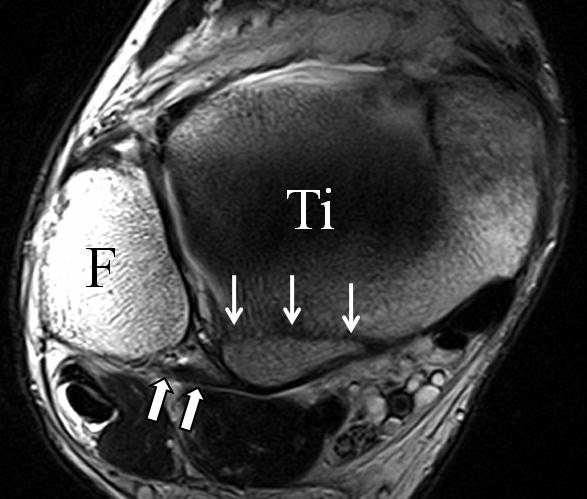

Die Kombination aus 3 Tesla Hochfeldtechnik und/oder Verwendung hochauflösender Spulen (Empfangseinheiten des Signals) erhöht die Signalausbeute. Dies erlaubt mit akzeptablen Messzeiten (3-4 Minuten pro Sequenz) im Routinebetrieb eine Darstellung mit einer Schichtdicke von 1-2 mm und einer Ortsauflösung von 0,2 x 0,2 mm in der Schichtebene in den anatomisch am besten zeichnenden 2D Turbospinechosequenzen. Der Unterschied der diagnostischen Wertigkeit zwischen einer kernspintomographischen „Standarduntersuchung“ und einer HR-MRT wird besonders in der chondralen Diagnostik sichtbar (Abb. 1 a-c). Unter Verwendung von 3D Sequenzen, die jedoch entscheidende Schwächen bei der Darstellung der Ligamente aufweisen, werden sogar Schichtdicken weit im Submillimeterbreich erreicht. Eine weitere Erörterung der Sequenz spezifischen Eigenheiten soll jedoch an dieser Stelle unterbleiben.

Das Ligamentum fibulotalare anterius entspricht einer bifaszikulären Struktur (Abb. 2 a) mit interponierendem fibrovaskulärem Gewebe (S. K. Sarrafian (ed). 2003). Es gibt jedoch Variationen der Ligamentanatomie. In 55% liegt das LFTA als bifaszikuläres Band (Abb. 2 a), in 9% als monofaszikuläre Bandstruktur (Abb. 2 b) und in 36% als multifaszikuläre, striäre Variante (Abb. 2 c) vor 3.

Das LFTA verbindet die antero-inferiore Fibulaspitze mit dem Processus lateralis tali und inseriert hier an einem oder zwei kleinen Tuberkeln 3. Der in Neutralposition horizontale Verlauf erleichtert die kernspintomographische Darstellung in dieser Standardebene. Das LFTA weist durchschnittlich eine Breite von knapp über 2 mm auf 4. Somit sind bei einer Routinedarstellung in 3 mm Schichtdicke Anschnittsphänomene, die die Diagnostik erschweren, regelmäßig anzutreffen. Dementsprechend sind auch die ligamentären Subfaszikel nicht zu differenzieren. In koronarer Darstellung ist dies aufgrund der hohen Auflösung in der Schichtebene jedoch möglich (Abb. 2 a-c), wobei hier wiederum eine Integritätsbeurteilung des Bandes erschwert ist. Unter Verwendung hochauflösender Techniken im Millimeterbereich (Schichtdicke) sind hingegen auch in der axialen Ebene die subfaszikulären Strukturen zu beurteilen (Abb. 3).